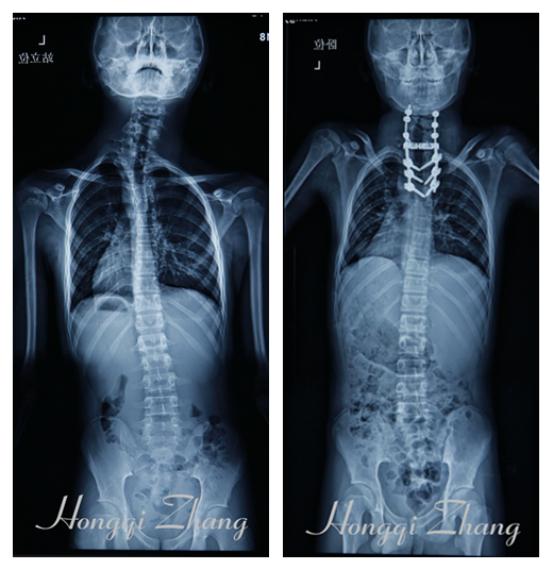

△术前、术后对比图

经过专业的治疗及精心护理,小宇术后身体状况得到迅速恢复,双肩等平,脖子完全正了。

术中张宏其教授仔细保护脊柱周围重要结构,按术前计划,顺利的对小宇先天性颈胸交界段脊柱实施了单纯经后路颈7胸1畸形融合椎体的椎骨部分切除及左侧第一肋的部分切除、脊柱三柱截骨、内固定矫形、植骨融合手术。

经过团队6小时的通力合作,手术最终取得圆满成功,安全地“打断”了畸形的脊柱,又完美地接合、矫正了脊柱畸形。